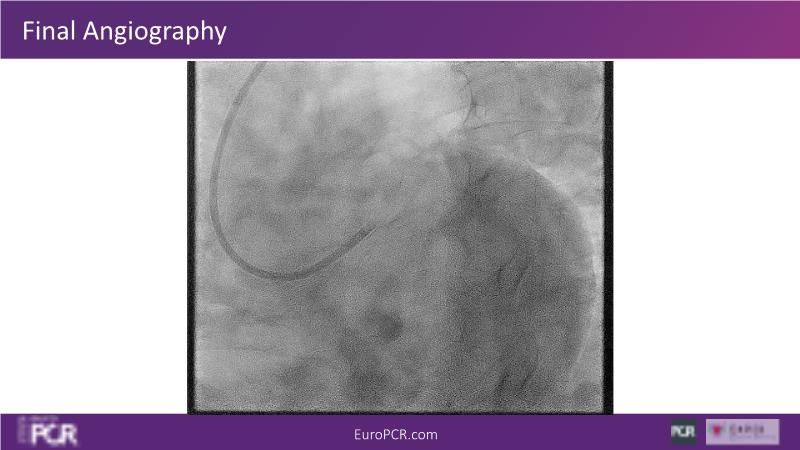

In this session, discover that provisional stenting in routine non-LM bifurcation using Resolute Onyx DES yields good mid-term outcomes without side branch intervention, provided the stent is sized to the distal reference and the side branch remains patent after a systematic POT. Learn how bifurcation stenting on a beating heart improves procedural understanding and adaptability. Additionally, explore how FFRangio offers high diagnostic accuracy in assessing physiological bifurcation lesions from angiograms without the need for hyperemia or a wire.